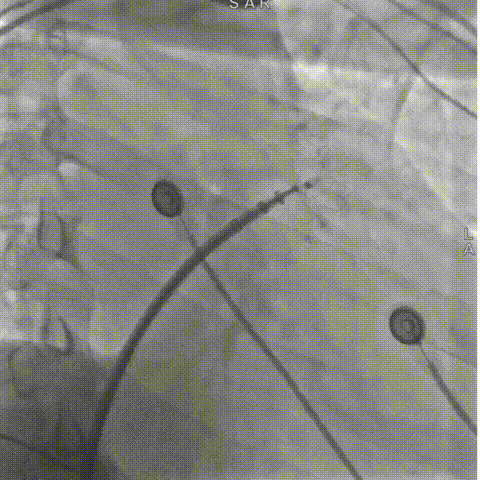

LAMax LAAC® 2430 Normal封堵器封堵盘在DSA下牵拉15s,锚定伞稳定无移位。

牵拉实验

符合COVER原则,将LAMax LAAC®2430 Normal封堵器释放,再次DSA造影检查,封堵器形态无变化,封堵效果好。

释放封堵盘

释放后造影